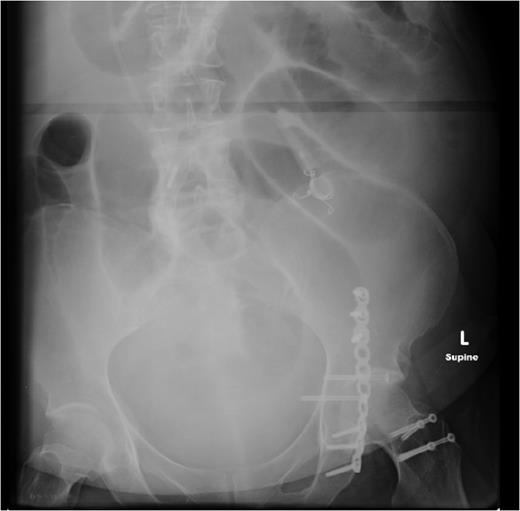

Two weeks later, she re-presented to the emergency department with a 24-hour history of severe central abdominal pain associated with vomiting and multiple episodes of loose stools. On examination, she was found to be hypotensive, tachycardic and peritonitic. The suspicion of an SBO was established by plain film radiograph appearances with multiple air fluid levels and distended bowel loops (Fig. 1). Computed tomography scan of the abdomen and pelvis showed the transitional zone to be in mid abdomen (Fig. 2). This was thought to be most likely secondary to adhesions. She proceeded on to have an emergency laparoscopy. Interestingly, the laparoscopy identified the transition point of the SBO to be an adhesion formed between the LAGB tube, the mid jejunum and the stomach forming a classic closed-loop obstruction (Fig. 3). The laparoscopic division of this adhesion was performed successfully. The rest of the small bowel was run along its entire length with no other transition point found. The adjustable gastric band was removed at the same time along with the associated port. Postoperatively, she had an uncomplicated recovery and was discharged on Day 4 post-admission without further sequelae.

The gastric band connection tube had formed a dense adhesion to the jejunum resulting in a tight obstructive band.